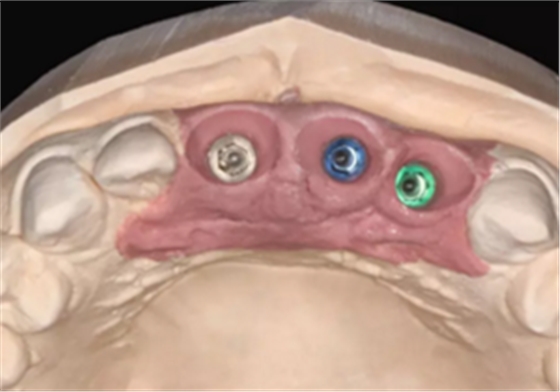

图5 设计种植体位置与多级导板

图6 设计临时修复体

(1)术前准备。拍摄临床照片、拍摄轻开口位CBCT(NewTom)、取聚醚印模灌制超硬石膏模型。 构建数字化模型并设计修复体:将超硬石膏模型在口外扫描(Identica? Hybrid),获取软硬组织表面形态,构建数字化模型,确认咬合情况。根据 天然牙残根颈部形态设计修复体颈部形态,使修复体颈缘轮廓与原有天然牙 一致;按正常牙弓弧度与覆 、覆盖关系,结合红白美学等原则确定修复体 的三维形态。最后,导入患者面部照片,确认模拟修复效果。 设计种植体位置并制作多级导板:利用Segma设计软件,将CBCT数据 和模型扫描数据进行配准,调入模拟修复效果数据,以修复为导向设计种植 方案,设计种植体螺丝孔开口从修复体舌窝处穿出,最终实现螺丝固位的一 体化基台冠修复。根据种植体信息设计多级导板,参考修复体形态设计导板 植入区颈缘外形,打印生成种植导板(Segma),并安装金属引导环。 设计并制作临时修复体:如前所述,按照美学效果和咬合关系设计临 时冠外形,颈部形态与模型龈缘轮廓一致,保证临时修复体在术后可以封闭 拔牙窝。3颗临时冠为连冠,龈外展隙适当加大,为术后软组织生长提供一 定的空间。在临时冠近两侧邻牙的切角处预留翼板,保证临时冠戴入时可以 找到准确的位置。以铣削的方式加工临时冠(Segma),待种植体植入后 将其在口内粘接于临时基台上。

本病例为上颌多颗相邻前牙因外伤致冠根折的病例,进行了“精确 化”的即刻种植修复。术前依据模型扫描数据、CBCT数据等构建数字化模 型,根据美学和功能原则设计最终修复体外形,再以修复为导向设计种植体 的三维位置,并制作多级导板,以提高种植体的植入精度。同时,为了减少 术后进行临时修复的等待时间,术前设计制作了高精度的临时修复体,修复 体颈部外形严格复制天然牙颈部轮廓,保证临时修复体术后可以严密封闭拔 牙窝;在临时修复体与临时基台之间预留一定间隙以便于口内就位和粘接; 在修复体近邻牙侧预留翼板以便于修复体的稳定就位。通过此类细节的处 理,可以保证在种植术后最短的时间内顺利戴入理想的临时修复体。